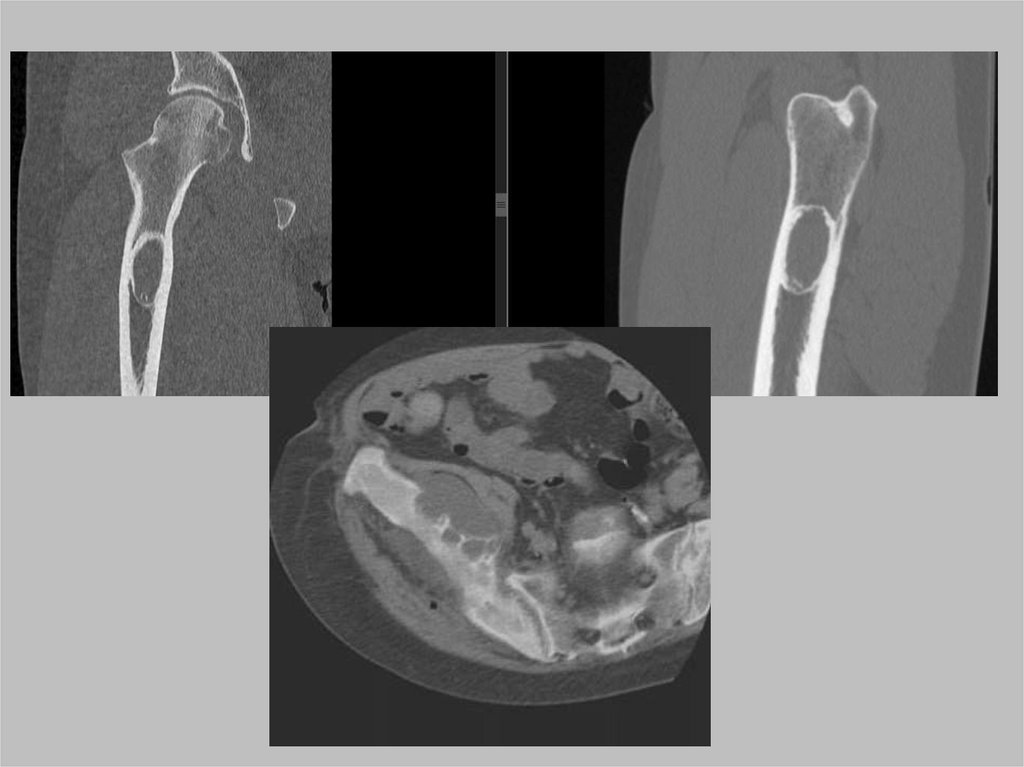

Костная патология

1.

2.

3.

4.

Перелом головки, шейки, костей таза

Лонные кости

Мягкие ткани в окрестности сустава

Органы малого таза на захваченных срезах